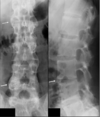

Natural history of untreated Ankylosing Spondylitis

Spinal enthesitis -> Bridging syndesmophytes (new bone growth between adjacent vertebra) -> Spinal fusion

Spinal MRI in Ankylosing Spondylitis-Advantage over Xray? What is an MRI sign of AS on MRI?

MRI can detect spinal inflammation before X-rays changes develop In image we see “Shiny corners” sign at L4, L5 and S1